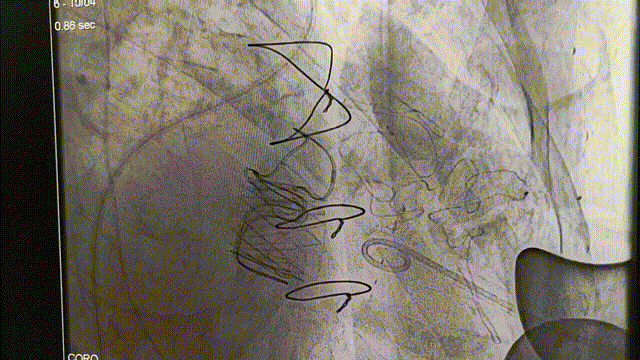

冠脉造影:左主干未见明显狭窄,前降支未见明显狭窄,血流TIMI3级,回旋支中段约40%狭窄,血流TIMI3级,右冠状动脉中段远段闭塞,血流TIMI0级。

DSA引导下定位心尖,心尖穿刺后置入泥鳅导丝及导管。利用导丝导管配合,穿过二尖瓣生物瓣。通过二尖瓣后置换加硬导丝。沿加硬导丝,置入J-Valve植入器。术中,通过观察定位件跳动的形态判断瓣膜位置,同时可以清晰感觉到力的反馈。定位件稳稳锚定原瓣架,可看到三个定位件随着心脏搏动而自然摆动。确定好位置后释放瓣膜,锁丝脱钩,瓣膜与植入器完全分离。观察瓣周漏与瓣膜形态,经食管超声心动图显示瓣膜位置合适,形态良好,无瓣周漏和反流。

定位件锚定原生物瓣瓣架